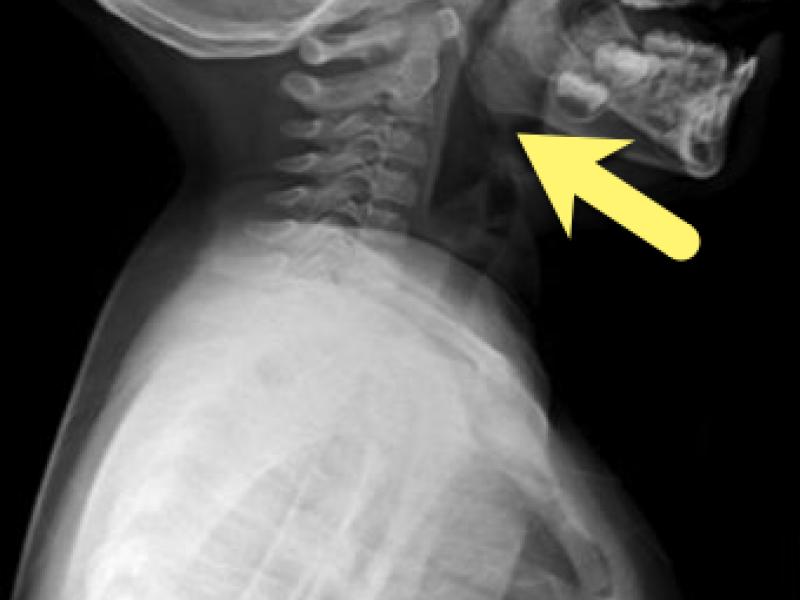

Diagnosis: Fishbone lodged in oropharynx A patient's